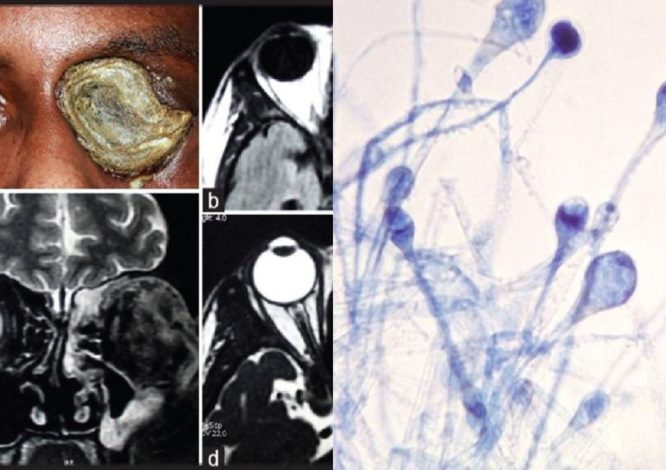

پزشکان باید بافت‌های مرده ناشی از عفونت را به سرعت از بدن بیمار جدا کنند. در برخی موارد لازم است بخشی از صورت بیمار برداشته شود تا قارچ به مغز نفوذ نکند. گاه عفونت در حدی پیش‌روی می‌کند که پزشکان ناچار می‌شوند چشم‌های بیمار را تخلیه کنند.

از آنجا به این عفونت تهاجمی است، باید هرچه سریع‌تر از بین برود و بافت‌های مرده نیز برداشته شود. به همین دلیل گاه جراحان مجبور می‌شوند بینی، چشم یا حتی فک بیماران را بردارند تا جلوی رسیدن عفونت به مغز را بگیرند.

مرکز کنترل و پیشگیری از بیماری‌های عفونی آمریکا (CDC) می‌گوید قارچ سیاه در کپک و مواد آلی پوسیده در خاک وجود دارد و از طریق استنشاق یا بریدگی و زخم‌های پوستی وارد بدن انسان می‌شود و روی سینوس‌ها تاثیر می‌گذارد.

در مورد علائم قارچ سیاه باید گفت این عفونت روی سینوسها، مغز و ریه‌ها تاثیر می‌گذارد و می‌تواند در افراد دیابتی یا دارای نقص شدید ایمنی مانند بیماران سرطانی یا مبتلایان به HIV/ AIDS خطرناک باشد. پزشکان مظنون هستند که ممکن است ارتباطی میان این بیماری و دارو‌های استروئید (کورتون) که برای درمان کووید به کار می‌رود وجود داشته باشد.